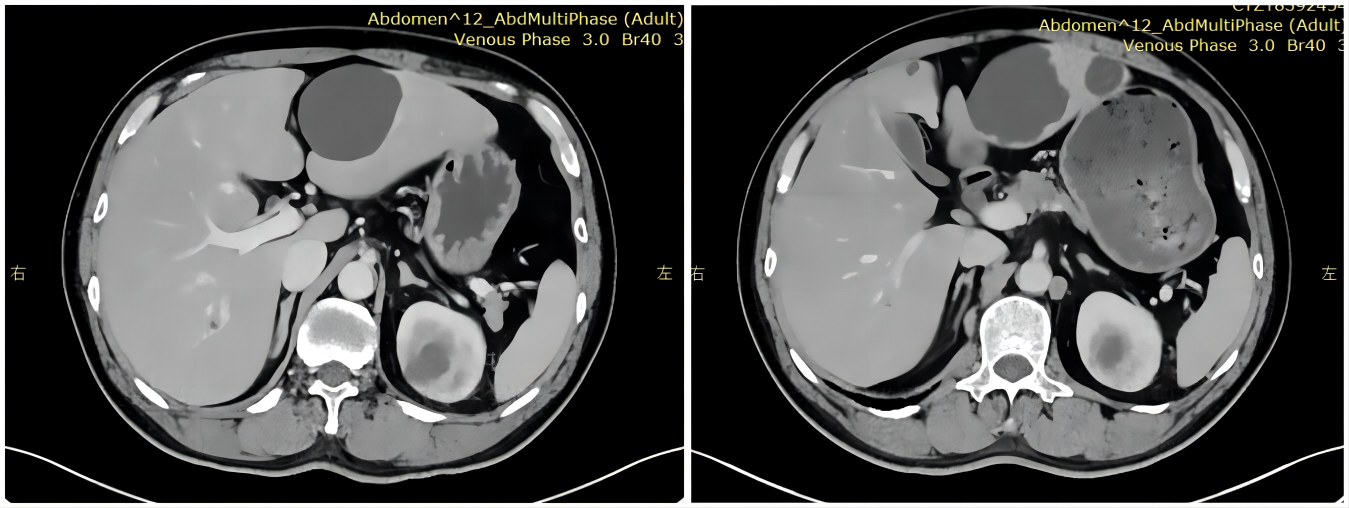

调整用药方案后,患者未再发热,CRP持续下降,由89.1 mg/L(2023-09-18)下降至20.5 mg/L(2023-09-21)。2023-09-21患者家属要求停用依拉环素,停用后患者CRP出现反弹,次日升至46.9 mg/L,予改回依拉环素治疗至足疗程(7天),改回后患者CRP再次下降至17.8 mg/L(2023-09-24)。2023-09-25复查增强CT,左肾上极囊肿伴感染较前(2023-09-16)好转(图3)。

图3. 增强CT检查(左:2023-09-16,右:2023-09-25)